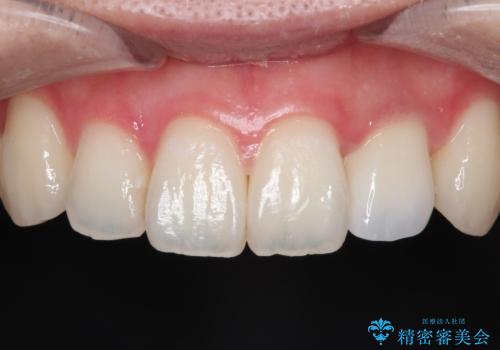

前歯の変色 オールセラミッククラウン

- 前歯の変色を主訴に来院されました。

根管治療後、オールセラミッククラウン(エクセレント)にて治療を行なっています。

オールセラミッククラウン(エクセレント)は、技工士さんが立会う事で色調や形態の相談を行うことができ、満足度の高い治療を行うことができます。